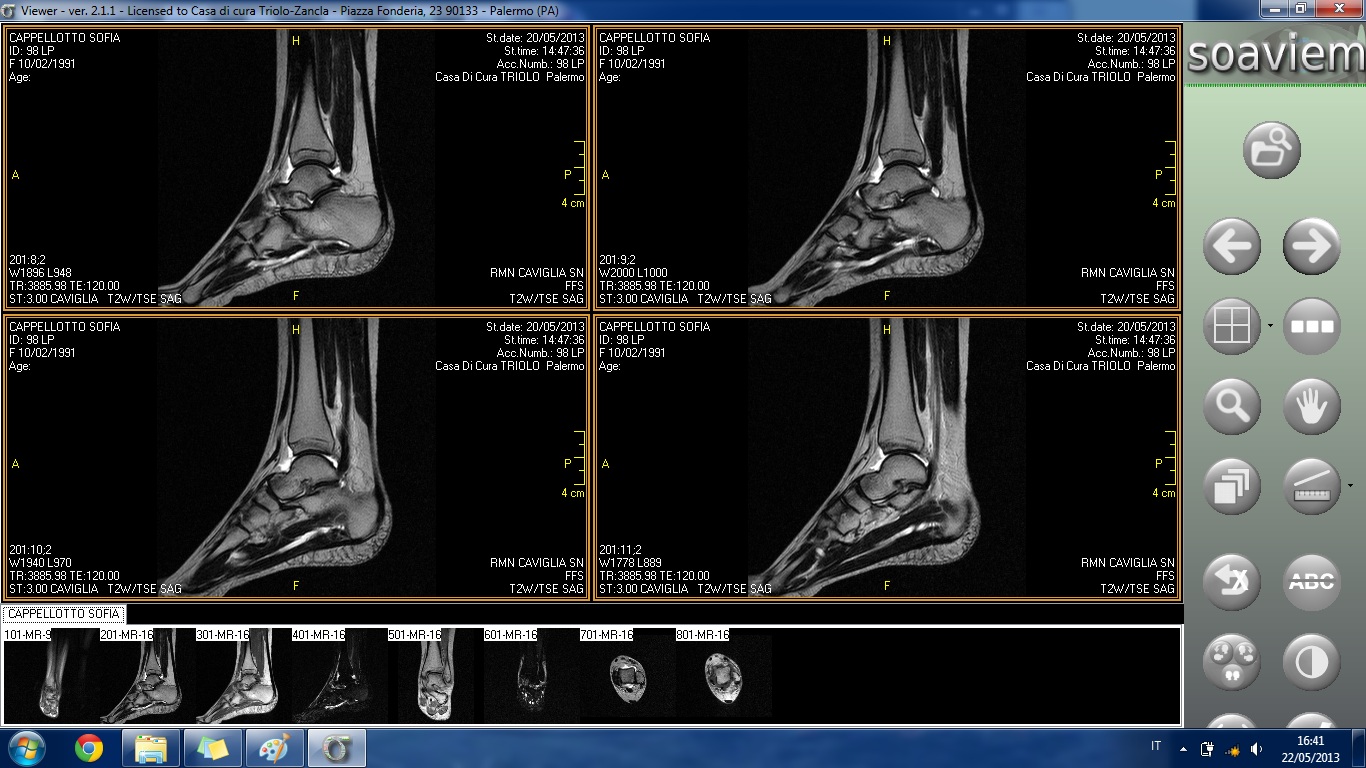

HO FATTO UNA RISONANZA E RIPORTO DI SEGUITO INDICAZIONI TRATTE DAL REFERTO E ALLEGO ALCUNE IMMAGINI:

ESAME ESEGUITO IN TECNICA SE, TSE E STIR MEDIANTE SCANSIONI T1 E T2 PESATE CONDOTTE SUI PIANI ASSIALE, CORONALE E SAGITTALE.

ALTERAZIONE DI SEGNALE DELLA TESTA ASTRAGALICA IN RELAZIONE ALLA PRESENZA DI AREA DI ELEVATO SEGNALE IN STIR DA RIFERIRE AD IPEREMIA TRABECOLARE COME IN ESITI DI IMPATTO OSSEO. REPERTO DI ANALOGHE CARATTERISTICHE DI SEGNALE SI RIVELA A CARICO DEL VERSANTE ANTERIORE DELL'EPIFISI DISTALE DELLA TIBIA ED A CARICO DEL MALLEOLO PERONEALE.

SENSIBILE QUOTA FLUIDA ENDOARTICOLARE.

IL LEGAMENTO PERONEO-ASTRAGALICO ANTERIORE NON APPARE IDENTIFICABILE NELLA PROPRIA CONTINUITÀ ANATOMICA COME PER LESIONE. TUTTAVIA IN RELAZIONE AL RECENTE EPISODIO TRAUMATICO SI CONSIGLIA RIVALUTAZIONE ETG A DISTANZA DI TEMPO. IL LEGAMENTO PERONEO-ASTRAGALICO POSTERIORE ED IL LEGAMENTO DELTOIDEO, SEPPURE INSERITI, MOSTRANO ASPETTO DISOMOGENEO COME PER ESITI DISTRATTIVI.

BEN INSERITO IL LEGAMENTO PERONEO-CALCANEARE.

REGOLARE ASPETTO DEL LEGAMENTO TIBIO-PERONALE INTERNO.

REGOLARE ASPETTO MORFOSTRUTTURALE DEI TENDINI PERONEI E DEI TENDINI DEL COMPARTO ANTERIORE E MEDIALE NEL TRATTO ESPLORATO.

SOSTANZIALMENTE REGOLARE ASPETTO MORFOSTRUTTURALE DEL TENDINE ACHILLEO.

NON SIGNIFICATIVE ALTERAZIONI DEL TROFISMO DEI RESTANTI CAPI SCHELETRICI ESAMINATI.

REGOLARE ASPETTO DELLE STRUTTURE DEL SENO DEL TARSO.